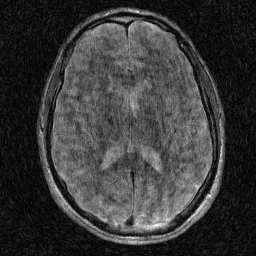

Magnetic Resonance Imaging (MRI) has excellent soft tissue contrast but is hindered by an inherently slow data acquisition process. Compressed sensing, which reconstructs sparse signals from incoherently sampled data, has been widely applied to accelerate MRI acquisitions. Compressed sensing MRI requires one or more model parameters to be tuned, which is usually done by hand, giving sub-optimal tuning in general. To address this issue, we build on previous work by the authors on the single-coil Variable Density Approximate Message Passing (VDAMP) algorithm, extending the framework to multiple receiver coils to propose the Parallel VDAMP (P-VDAMP) algorithm. For Bernoulli random variable density sampling, P-VDAMP obeys a "state evolution", where the intermediate per-iteration image estimate is distributed according to the ground truth corrupted by a zero-mean Gaussian vector with approximately known covariance. To our knowledge, P-VDAMP is the first algorithm for multi-coil MRI data that obeys a state evolution with accurately tracked parameters. We leverage state evolution to automatically tune sparse parameters on-the-fly with Stein's Unbiased Risk Estimate (SURE). P-VDAMP is evaluated on brain, knee and angiogram datasets and compared with four variants of the Fast Iterative Shrinkage-Thresholding algorithm (FISTA), including two tuning-free variants from the literature. The proposed method is found to have a similar reconstruction quality and time to convergence as FISTA with an optimally tuned sparse weighting and offers substantial robustness and reconstruction quality improvements over competing tuning-free methods.